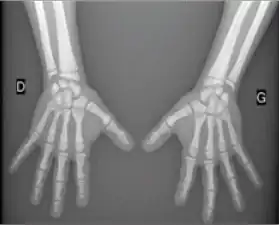

Acroosteolysis

Acroosteolysis is resorption of the distal bony phalanges. Acroosteolysis has two patterns of resorption in adults: diffuse and bandlike.

The diffuse pattern of resorption has a widely diverse differential diagnosis which includes: pyknodysostosis, collagen vascular disease and vasculitis, Raynaud's neuropathy, trauma, epidermolysis bullosa, psoriasis, frostbite, sarcoidosis, hypertrophic osteoarthropathy, acromegaly, and advanced leprosy.[1][2][3]

The bandlike pattern of resorption may be seen with polyvinyl chloride exposure and Hadju-Cheney syndrome.[1]